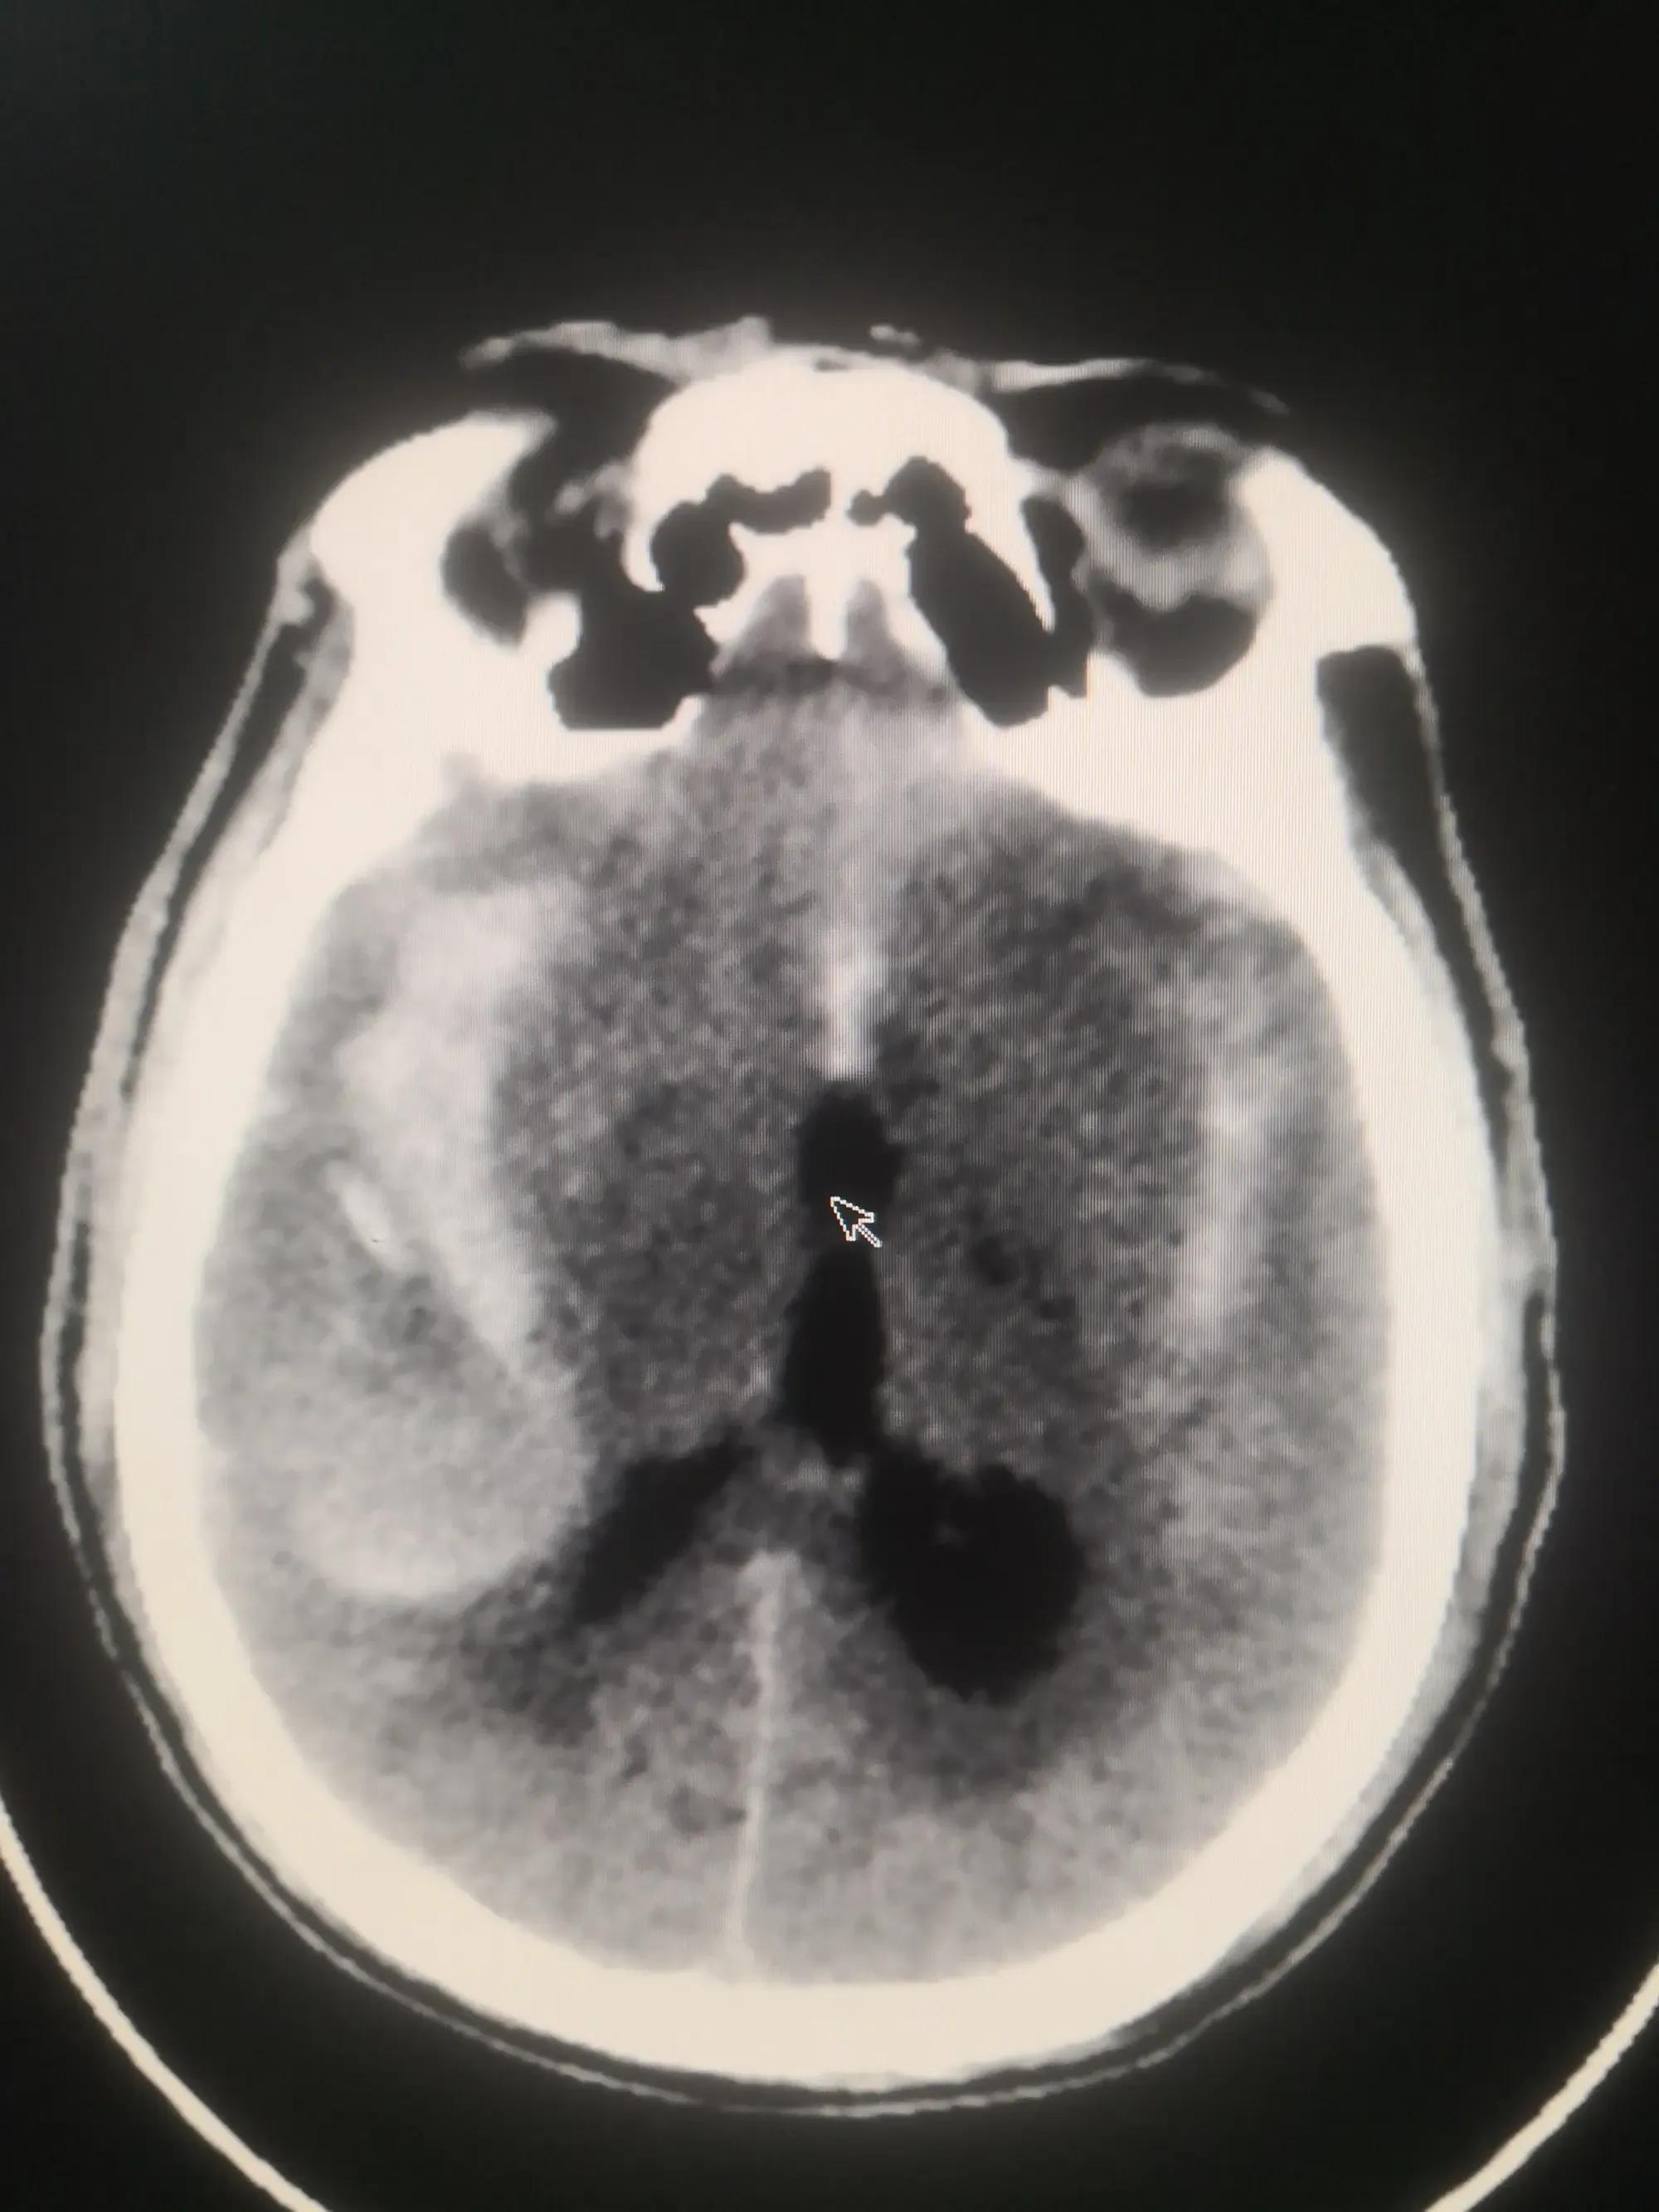

(1).头颅CT:诊断动脉瘤破裂引起蛛网膜下腔出血的首选方法。

蛛网膜下腔出血脑CT